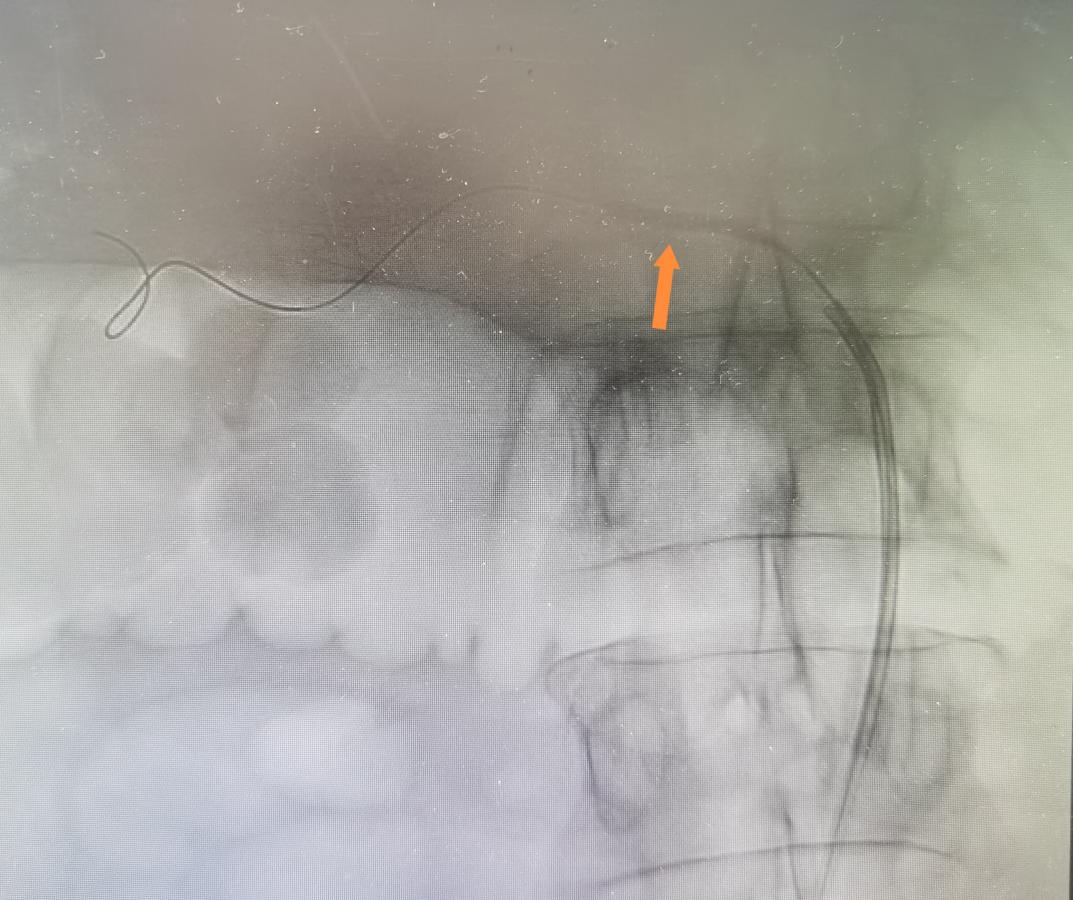

右肾动脉球囊扩张

狭窄扩张后已经显影